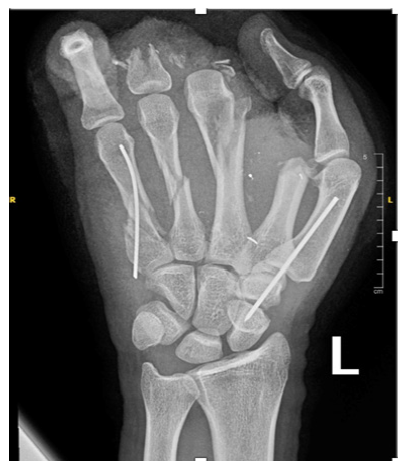

Regarding orthopedic surgical management, K-wires were initially used in 10 hands. Post operative X-Rays revealed 15 previously missed injuries (comprising 7 metacarpal fractures, 5 phalangeal fractures and 3 missed metallic foreign bodies). Of these 6 patients underwent secondary surgeries the following day, primarily for intramedullary pinning in case of metacarpal fractures (Figure 2), or standard pinning for phalangeal fractures while foreign bodies were removed at the bedside under local anesthesia.

Figure 2:Patient who presented with a severe injury and required revision surgery. A, B: Clinical status upon arrival. C, D, E: Post debridement and partial amputation. F: Post revision surgery the following day.